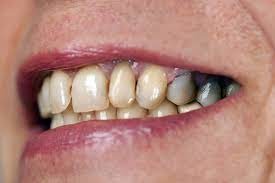

Black Teeth: Symptoms, Causes and Treatment

Black teeth can be a concern for many people; a black tooth will affect your smile and impact on your confidence. If you have a black tooth, read on to find out more about the symptoms and causes and treatments that may be available.

What causes a tooth to go black?

There are many reasons why a tooth can begin to go black, anything from simple staining to the death of the tooth can cause blackness and darkening.

Poor oral hygiene

Poor oral hygiene can cause your tooth to go black. In the early stages this is likely to be staining from substances like tobacco, red wine and strongly colored food. If your oral hygiene routine is not thorough enough to remove the acid-excreting bacteria each day, the acid will slowly eat away at your tooth.

As the tooth gets eaten away, tooth decay sets in. Tooth decay naturally looks black and can give the appearance of a black tooth. This gives the look of rotten teeth and is a classic result of not looking after your teeth for a considerable period of time.

The death of a tooth

When a tooth dies, the blood supply – which gives the tooth its natural, healthy color – will stop. Because the tooth is not receiving the nutrients it needs, it will begin to necrotise, darken, die and slowly go black.

Will my tooth go black after root canal?

A common misconception is that a tooth will go black after a root canal treatment. Teeth will often go black before root canal treatment as the tooth rots and decomposes on the inside. If root canal treatment is done well, all of the decomposing tissue will be removed and the blackness will not get worse. There may, however, be some mild darkening of the tooth after a root canal, depending on exactly how the root canal treatment is done and with which material.

How long does it take for a tooth to go black?

If the cause of the blackness is due to tooth decay, the blackness can happen over a period of years. If the cause of the blackness is due to trauma, as soon as the blood supply has been cut off from the tooth, the internal tooth tissue will begin to die and turn black.

Will a dead tooth go black?

If a dead tooth is left untreated, it will go black as the internal tooth tissue dies and decomposes. If the dead tooth has been root treated with a tooth-colored treatment, the tooth may not go completely black, although it may darken slightly.

Treatments for a black tooth

Black spots on teeth can be treated quite simply, these can often be caused by a small pit or chip in the tooth which either picks up staining or has a small amount of decay. Your dentist can usually remove a small amount of tooth around this area, removing the staining and/or decay and placing a some tooth-colored bonding material over this area. The tooth bonding will blend in naturally with your surrounding teeth, making the repair invisible.

Dead tooth whitening is also possible. This is whitening with a peroxide gel which can whiten teeth significantly; however, sometimes teeth whitening alone is not enough to whiten a dead tooth and some form of restorative option needs to be considered, either a dental veneer or a dental crown.